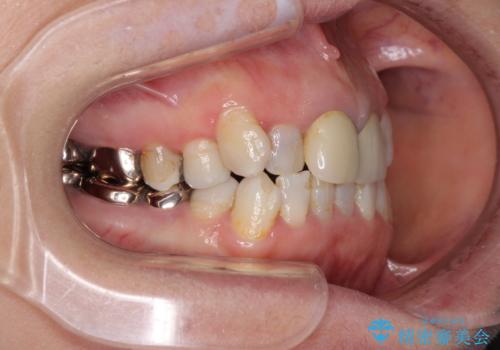

- 全顎的な歯列不正と、銀歯だらけの奥歯を気にして来院された患者様です。

奥歯の銀歯は、セラミッククラウンを装着するには歯の高さが不十分であり、そのままでは矯正治療を行うことが困難であるため、歯冠長延長術を行うこととしました。

また、根管治療の必要な歯がいくつかあるため、歯周外科治療の治癒期間を利用して根管治療を行い、その後インビザラインにて矯正治療を行うこととしました。

矯正治療後にはオールセラミッククラウンにて補綴治療を行うこととしました。

外科処置に対する恐怖心が強かったため、処置の際には静脈内鎮静法を用いて、リラックスした状態で行いました。